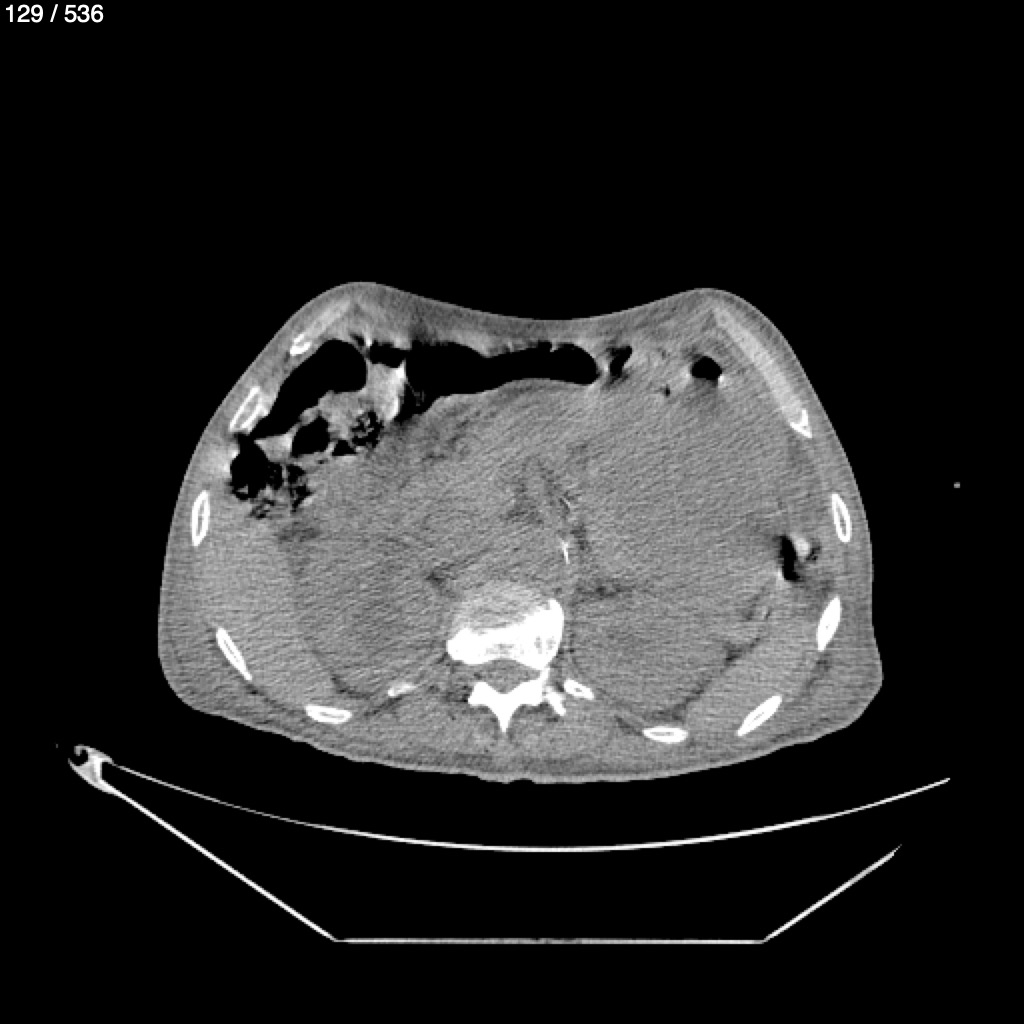

Angel Villalobos Palomeque 73 A - T.C Abdomen Simple